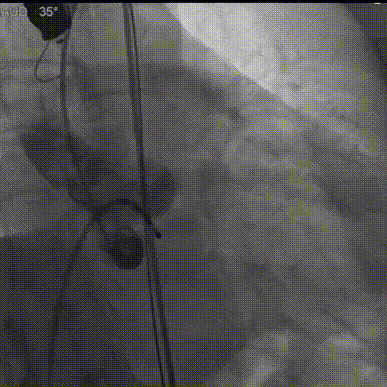

180bpm下置入23mm球囊扩张,沿导丝送入美敦力Evolut PRO经导管主动脉瓣膜系统,采用美敦力独有的commissural alignment技术,最大程度保护冠脉。递送系统顺利送入动脉系统并顺利过弓跨瓣,在最终目标位置完美释放,瓣膜立即工作。展开形态良好,无瓣周漏,无冠脉阻挡,无传导阻滞发生,术后无跨瓣压差,血液动力学稳定,手术圆满成功。

球囊扩张

过弓跨瓣